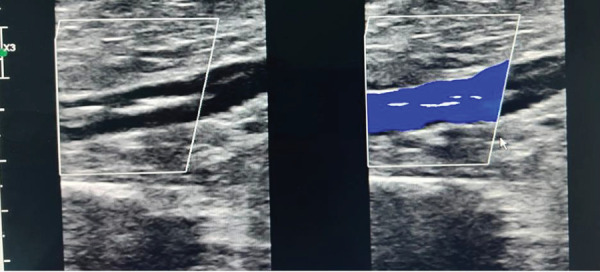

Introduction: Phlebolith is a term that refers to round-shaped calcified thrombi commonly located in the pelvic region. The occurrence of dense, linear calcifications or phlebolith-like formations within the soft tissues of the lower extremities, particularly in the superficial femoral, greater saphenous, or popliteal veins, is rare. Patient Concerns: This study presents the case of a 73-year-old woman who was being evaluated for postmenopausal bleeding. During the patient's diagnostic workup, an incidental linear-shaped phlebolith was discovered. She had a positive history of deep vein thrombosis (DVT) for 36 years following her previous vaginal delivery. Diagnosis: Upon further examination and imaging, the patient was found to have a chronic calcified thrombus in the iliofemoral, popliteal, great saphenous, and superficial femoral veins, which was initially reported as a foreign body in the femoral vein on computed tomography (CT). Interventions and Outcomes: Conservative management was undertaken, with no worsening of her condition upon further follow-up. Conclusion: This study showcased a rare form of a radiographically visible calcified thrombus in the veins of the lower extremities of our patient. Calcified venous thrombosis in the lower extremities is rare, as previously documented cases of venous calcifications have been observed in the pelvis with round shapes or as phleboliths. The common presentations differ from those in our case, making it important to consider such cases when formulating a differential diagnosis. While the precise mechanisms behind the formation of calcified thrombi remain unclear, this study emphasizes the significance of further exploration and future case studies to shed light on this enigmatic phenomenon.

导言:静脉结石是一个术语,指的是通常位于骨盆区域的圆形钙化血栓。在下肢软组织,特别是在股浅静脉、大隐静脉或腘静脉中,发生致密的线状钙化或静脉样形成是罕见的。患者关注:本研究提出了一个73岁的妇女谁是评估绝经后出血的情况。在病人的诊断检查中,偶然发现了线状静脉结石。她有深静脉血栓(DVT)阳性病史36年后,她的阴道分娩。诊断:经进一步检查和影像学检查,发现患者在髂股静脉、腘静脉、大隐静脉和股浅静脉有慢性钙化血栓,最初在CT上报告为股静脉异物。干预措施和结果:采取保守治疗,进一步随访时病情未恶化。结论:本研究显示了一个罕见的形式的钙化血栓在我们的病人的下肢静脉放射可见。下肢静脉钙化血栓是罕见的,因为以前有文献记载的静脉钙化病例在圆形骨盆或静脉结石中被观察到。常见的表现与我们的病例不同,因此在制定鉴别诊断时考虑这些病例很重要。虽然钙化血栓形成的确切机制尚不清楚,但本研究强调了进一步探索和未来案例研究的重要性,以阐明这一神秘现象。